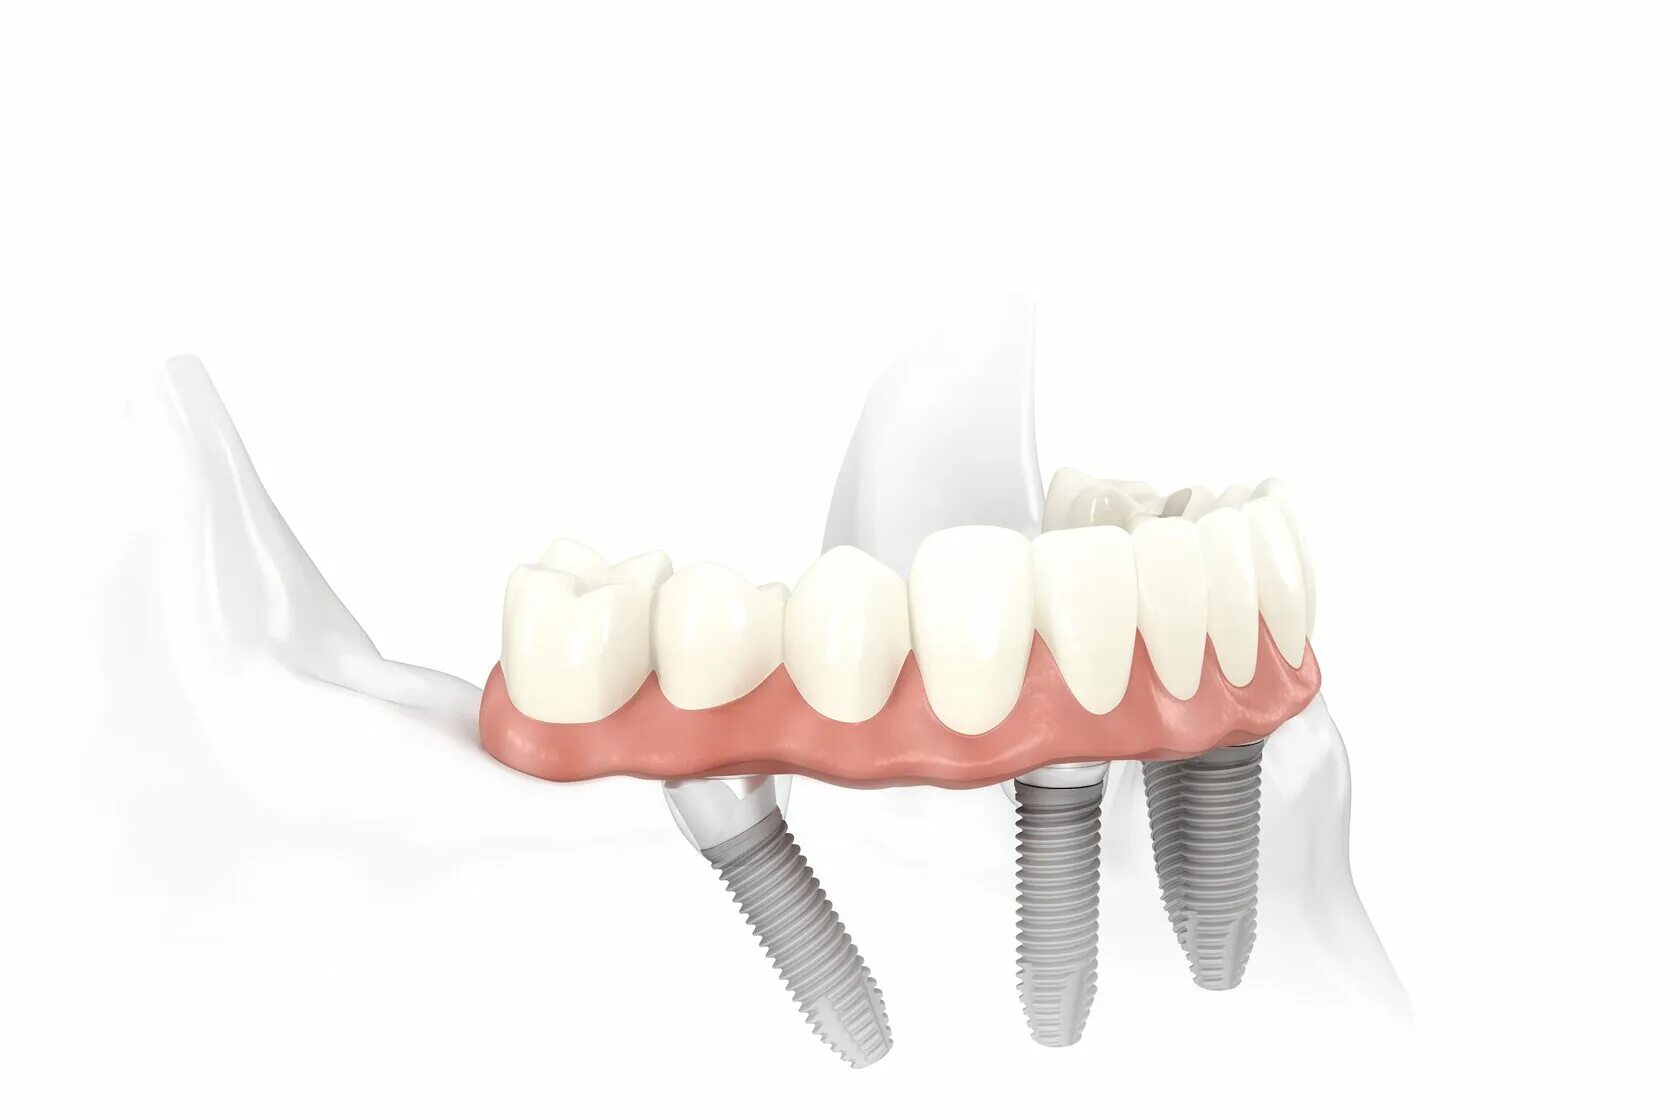

Ол он 4